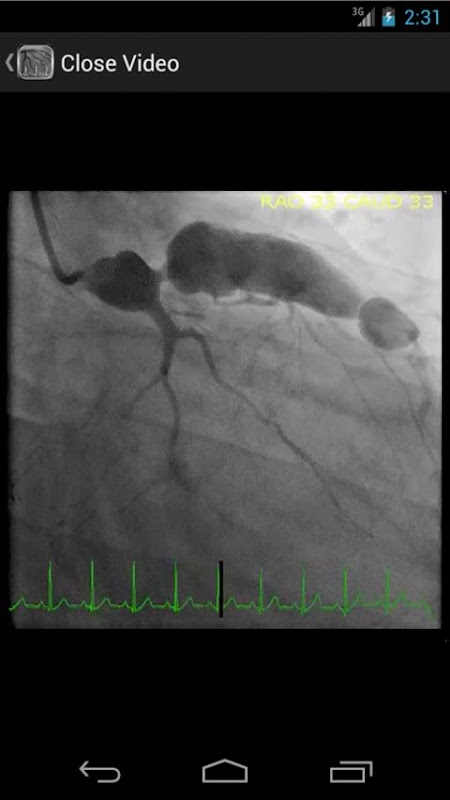

* Doorzoekbare database met meer dan 30 video's (coronaire angiografie, ventriculograms en aortograms) van zowel gemeenschappelijke als zeldzame bevindingen in het hartcatheteriserenlaboratorium

CathSource geeft een gedetailleerd overzicht van belangrijke hartkatheterisatie en angiografie onderwerpen, waarin educatieve afbeeldingen / video's en reviews van relevante medische literatuur. CathSource is de ideale toepassing om u te helpen bij het begrijpen en herkennen van cardiovasculaire pathologie in de catheterisatie lab.